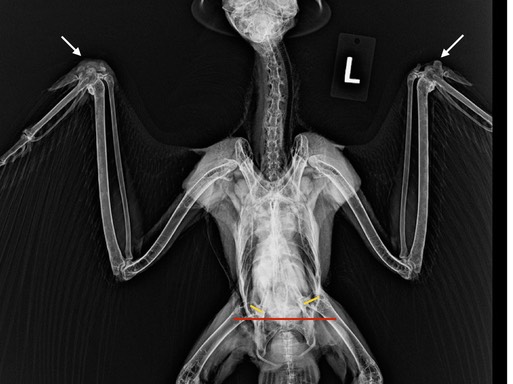

Red-tailed Hawk 21-757 is the only diurnal bird (active during the day) in the clinic. She was found near a freeway so likely was hit by a car. She has damage in her right wrist and the left side of her pelvis. If you look at the radiograph below you will see asymmetry between the wrists (white arrows) and in her pelvis. There is swelling in the right wrist and the alular metacarpal is fractured. The yellow lines show where the femurs articulate with the pelvis. The lines should be even, not offset. There is damage on the left side. It is likely the pelvis will heal and be functional. The prognosis for the wrist is more guarded, but the hawk is standing and eating, so we will see how she does.